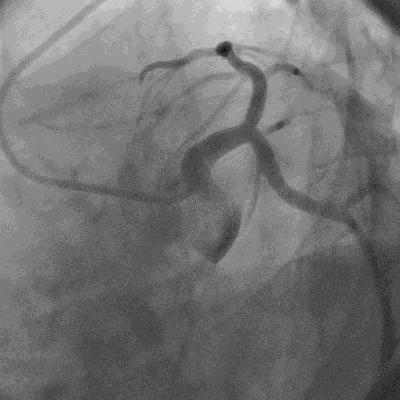

很快十八导心电图打印了出来,急性心肌梗死明确无疑,甚至考虑病变部位在左主干。

图文无关

一边抽血化验对症处理一边联系心内科积极准备介入治疗,这是对急性心肌梗死患者的常规诊治流程。

介入支架技术的出现让许多急性心肌梗死患者得以续命,让死神望而却步。

此刻,导致这位中年男性患者剧烈胸背痛的原因已经大致明确:急性心肌梗死。

但是,在明确诊断之前,还有一件事情是需要完成的,那就是排出主动脉夹层。

在人类的医学史上,在我所知道的范围之内,在我能够查阅导的资料之内,急性心肌梗死合并主动脉夹层或者因主动脉夹层而诱发心肌梗死的情况并非罕见。

心内科医生的会诊意见也是如此:排除主动脉夹层,介入手术治疗!